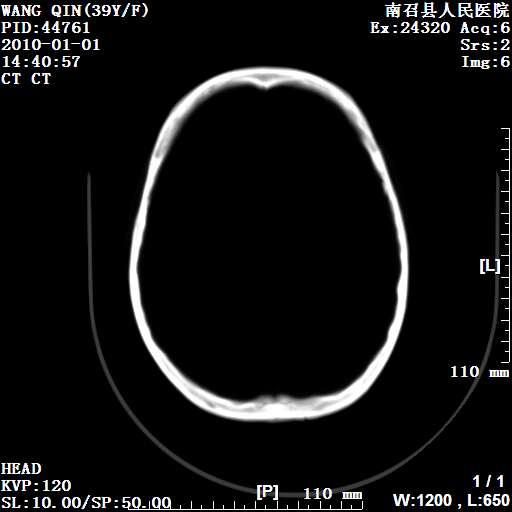

以下是引用随光逐影在2010-1-22 9:03:00的发言:[br]考虑左侧中颅窝(蝶骨翼区)脑膜瘤侵犯蝶骨翼并突入左侧眼眶。

以下是引用水过无痕在2010-1-22 14:55:00的发言:[br]一、定位:颅外占位;二、定性:恶性可能性大;三、组织来源:来源于左侧眼外直肌或其他部位;考虑为:横纹肌肉瘤>转移瘤>脑膜瘤.